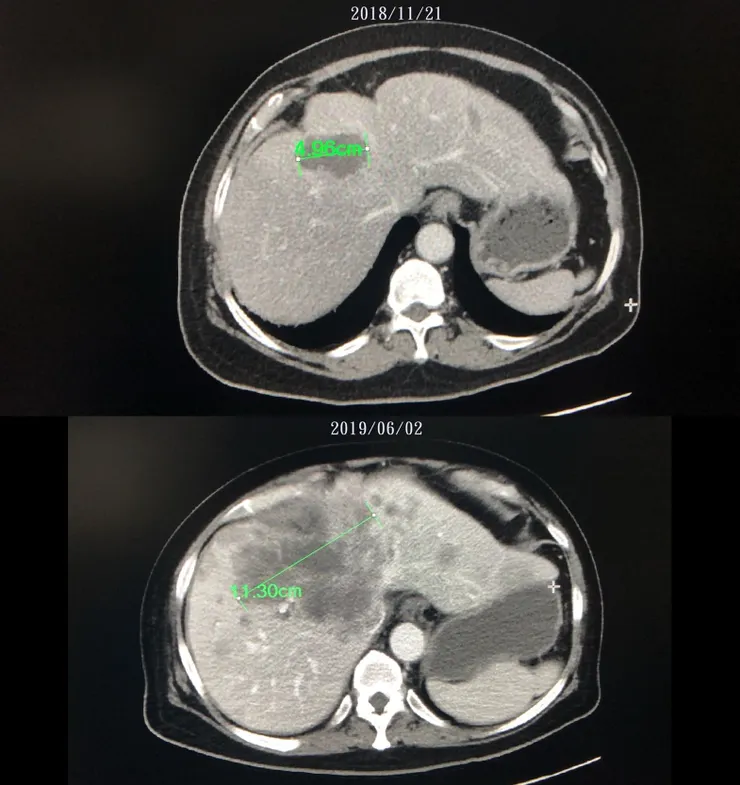

台大醫院澄清今年1月11日漏未做「肝腫瘤燒灼手術」(Radio Frequency Ablation, RFA),聲稱是考量病人情形已不適合再進行電燒;且事後於3月替病人進行全身性化療,6月也再進行電燒。台大醫院同時確認是有「誤植」診斷證明書的情形,並經家屬提醒,已做出修正,還建議家屬可到院更換診斷書。

此前,梁姓名醫曾說:「事實上按照學理來說,1月11日那次有電燒還是沒電燒也沒差多少。」但拖到6月,台大醫院還是對病人進行電燒,用以「補救」。

至於台大醫院所稱的補救措施,何姓病人質疑,原本1月要做的電燒,沒做的當下也不講,好幾個月之後被發現沒做,拖到6月才補做,「癌症治療可以這樣嗎?」